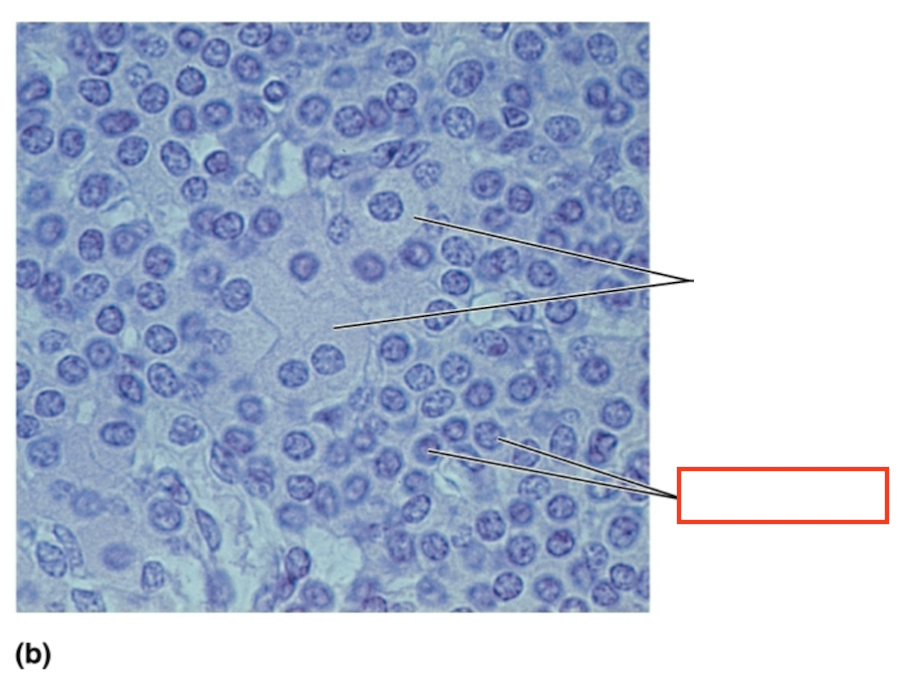

What structure is highlighted?

acidophils

What structure is highlighted?

chromophobe

What structure is highlighted?

basophil

What tissue is shown?

anterior pituitary